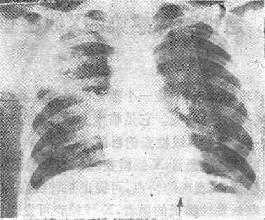

(三)段、叶性实变 多见于肺炎双球菌肺炎,可经过充血、红色肝变、灰色肝变及吸收消散四个时期。X线的特点是段、叶范围的实变,在叶间胸膜区界限清楚锐利,其他边界则模糊不清,病变区域内可见支气管气影征(air bronchogram sign)(图112-1)

图112-1 段、叶性实变之X线表现